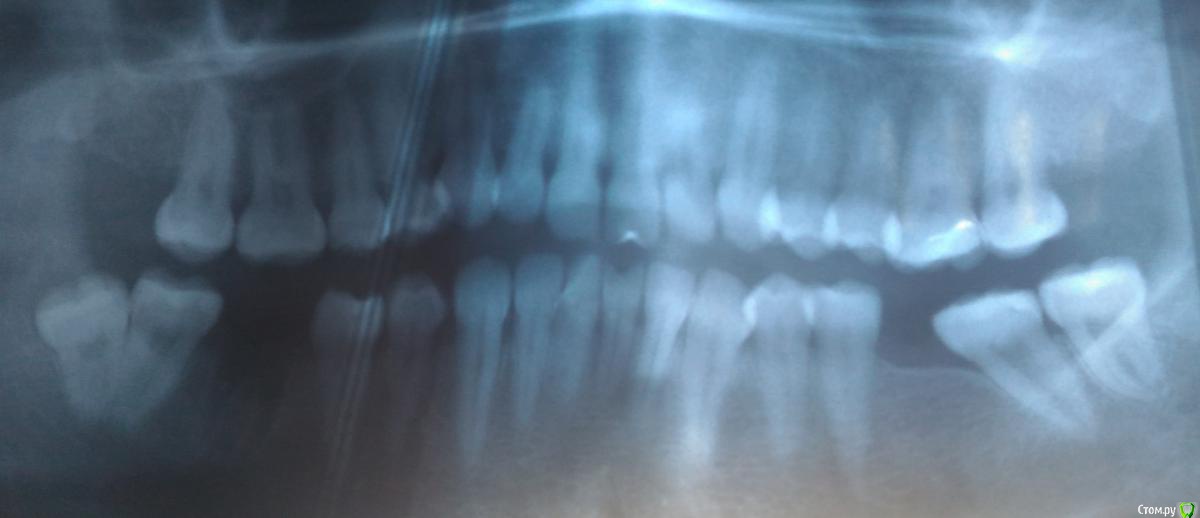

dim-nat Опубликовано 14 марта, 2017 Поделиться Опубликовано 14 марта, 2017 Добрый день! Планирую беременность, при плановом посещении стоматолога залечила кариес на 6 зубах, шестерку не спасли - удалили. Перед удалением сделала снимок и врач сказал, что нужно удалять восьмерку слева. Начиталась ужасов про удаление, нахожусь в предобморочном состоянии. Прошу Вашего мнения о сложности моего случая (читала, что бывает быстрое и долгое удаление) и необходимости удаления. P.S. До сего момента восьмерки не беспокоили, начитавшись же интернета начали ныть попеременно слева и справа. К сожалению, я подвержена истерии и приступам паники, боль практически не переношу. Ссылка на комментарий